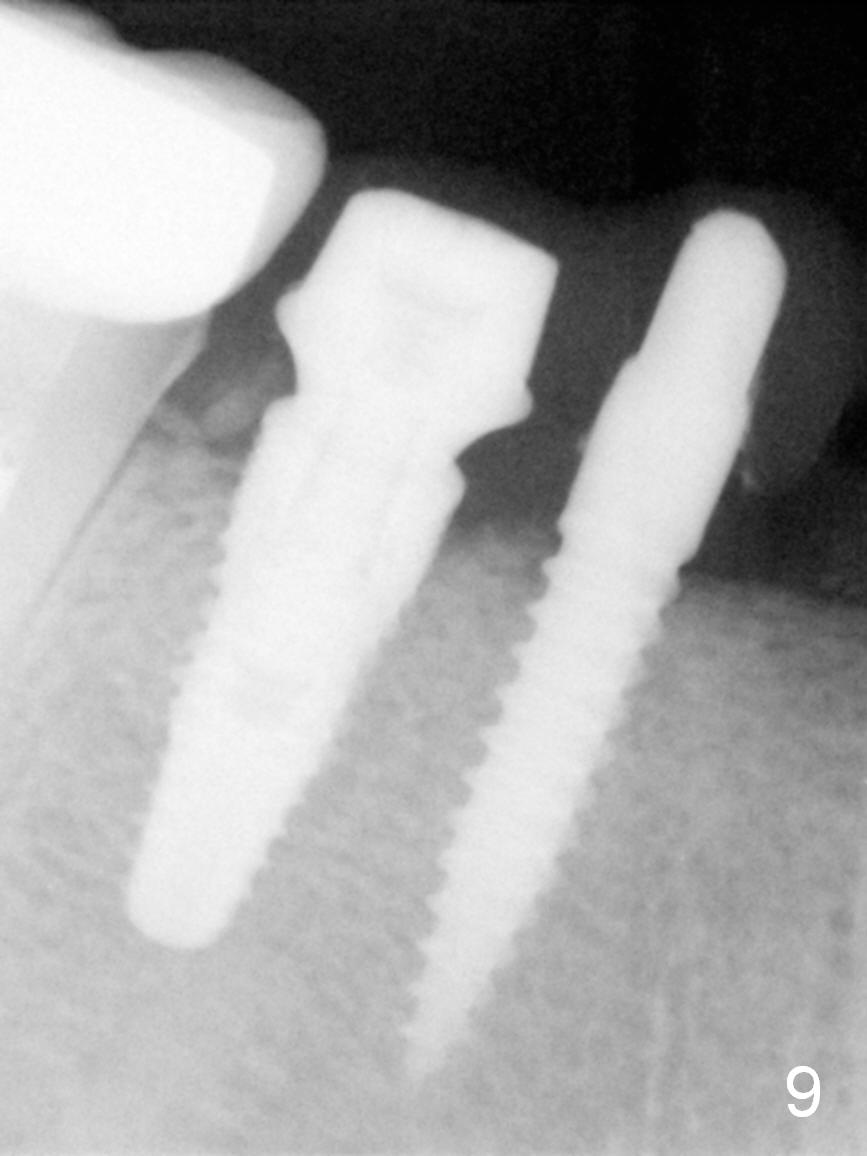

PA is taken 2.5 months postop (Fig.9). The definitive restorations are cemented 4 months postop. With placement of the implants and bone graft, the lingual tissue looks bulky (Fig.10 white arrowheads). Black arrowheads indicate that the ridge at #28 is narrower than that at #29, the anatomic base for 1-piece implant at #28. CT study reveals that the crest at the site of #20 appears to be narrower than that at #28. What is the treatment option?